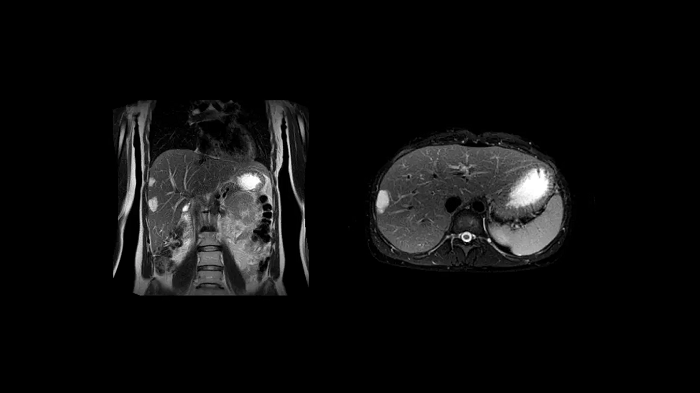

Abdomen

MRCP with Compressed Sensing

Abdominal imaging with T2w SPACE of the biliary ducts can be expedited with Compressed Sensing to reduce acquisition times. Both techniques offer high-resolution, high-quality MRCP for uncompromised abdominal investigation.

Compressed Sensing factor 6.5 | 1.2 x 1.2 x 1.0 mm3 | TA = 4:21 minutes

- Contour L Coil

- Spine Coil

Image Courtesy: University Hospital Erlangen, Germany | Image-ID: 4aaaa0465

T1 VIBE Dixon with CAIPIRINHA

Benefit from Siemens Healthineers’ dedicated CAIPIRINHA acceleration to gain a complete abdominal volume within a single breath-hold. The Dixon technique offers outstanding fat-water separation for a flawless representation of the abdominal anatomy.

- Contour L Coil

- Spine Coil

Image Courtesy: University Hospital Erlangen, Germany | Image-ID: 4aaaa0458

Body diffusion imaging

Outstanding quality diffusion imaging for comprehensive abdominal MR capabilities.

- Contour L Coil

- Spine Coil

Image Courtesy: University Hospital Erlangen, Germany | Image-ID: 4aaaa0339

T2 BLADE

T2 motion insensitive abdominal imaging using BLADE results in outstanding outcomes, regardless of the orientation or if fat saturation is needed.

- Contour L Coil

- Spine Coil

Image Courtesy: University Hospital Erlangen, Germany | Image-ID: 4aaaa0339